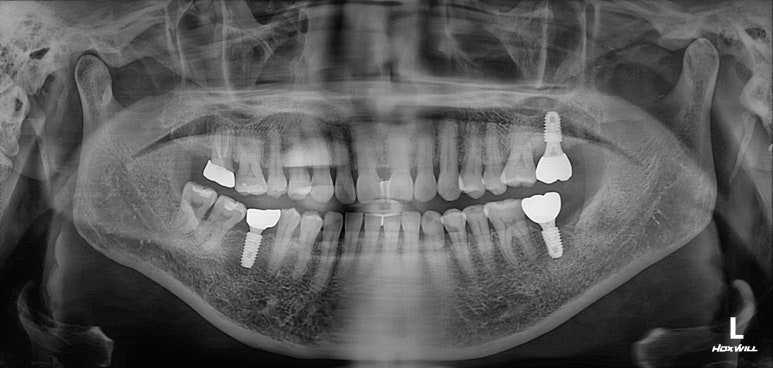

딱 봐도 치아가 조금 없는 것 같으시죠?

빨간색 동그라미로 표시된 곳에 치아가 없어요! 왼쪽 아래 두번째 어금니를 뽑으신 지 몇 년 지나신 상태였습니다.

노란색 동그라미로 표시된 치아는 뿌리만 있는 잔존치근 상태로, 살릴 수 없는 치아였어요.

그리고 마지막으로 파란색 동그라미로 표시된 치아는 기존 크라운 아래로 이차충치가 생겨서 신경치료가 필요한 상태!